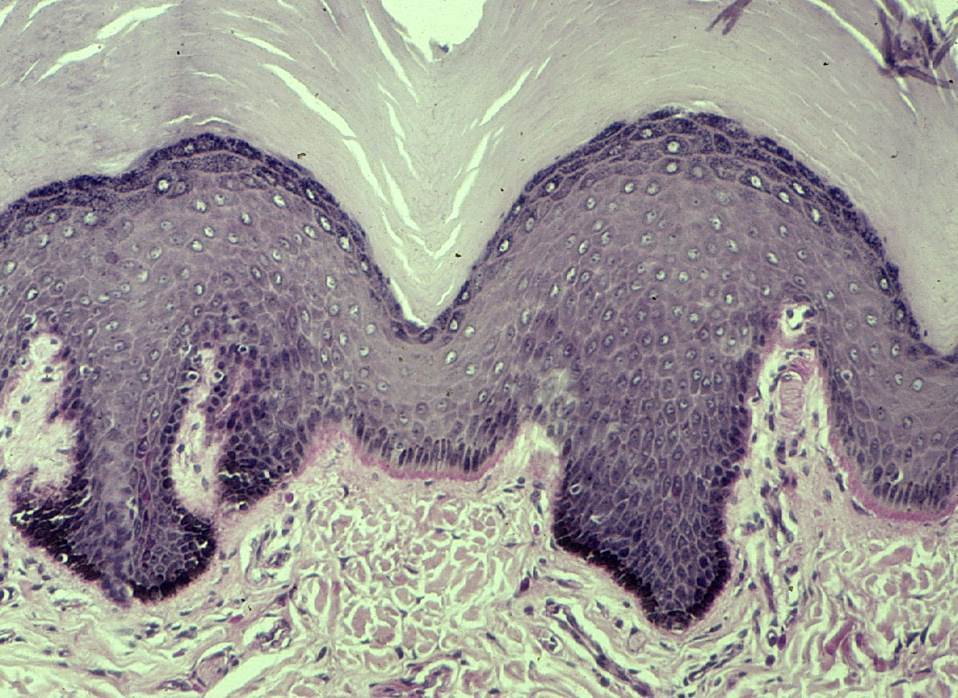

What is the makeup of the epidermis?

keratinizing, stratified squamous epithelium

What is the makeup of the dermis?

connective tissue/stroma

What are the four layers of the epidermis starting from the bottom? What happens in each layer?

basal layer (stratum basale) - proliferation

spinous layer (stratum spinosum) - adhesion

granular layer (stratum granulosum) - differentiation

stratum corneum (cornified layer) - death